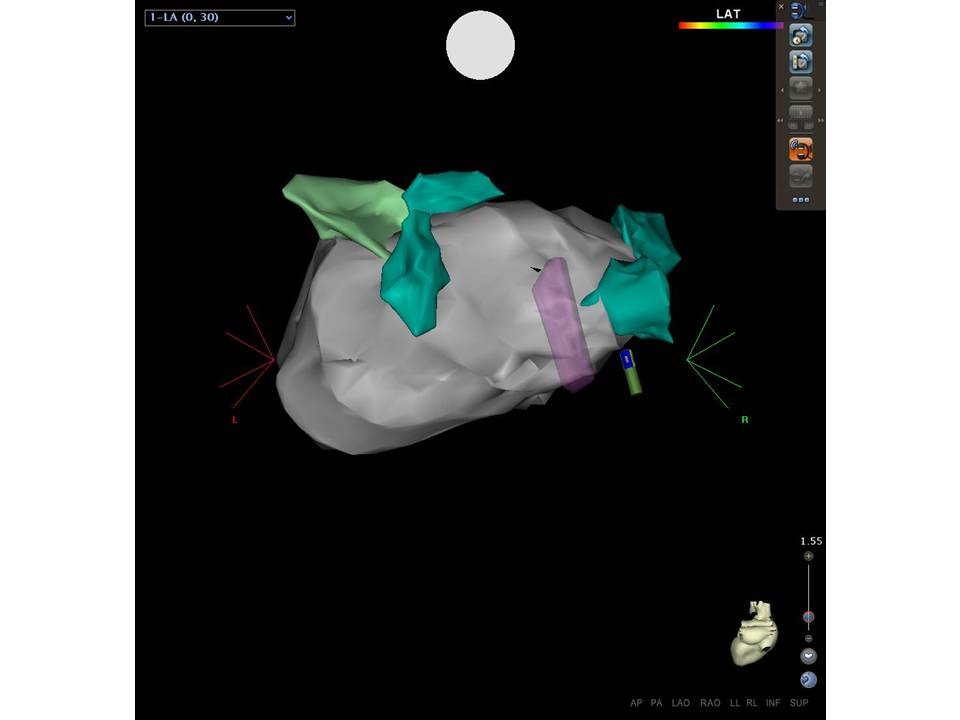

Use of ICE to Eliminate Radiation During AF Ablation

2015-07-24 13:06